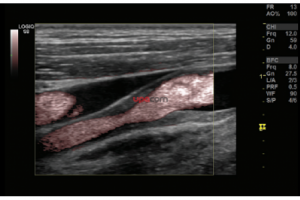

- Система Logiq S8 GE Healtcare, производства Россия – это уникальная ультразвуковая система экспертного класса, компактная и мобильная, удобная в эксплуатации.

- B-режим, M-режим, PW допплер, цветовое допплеровское картирование и энергетический допплер, кодированное излучение, кодированную тканевую гармонику.